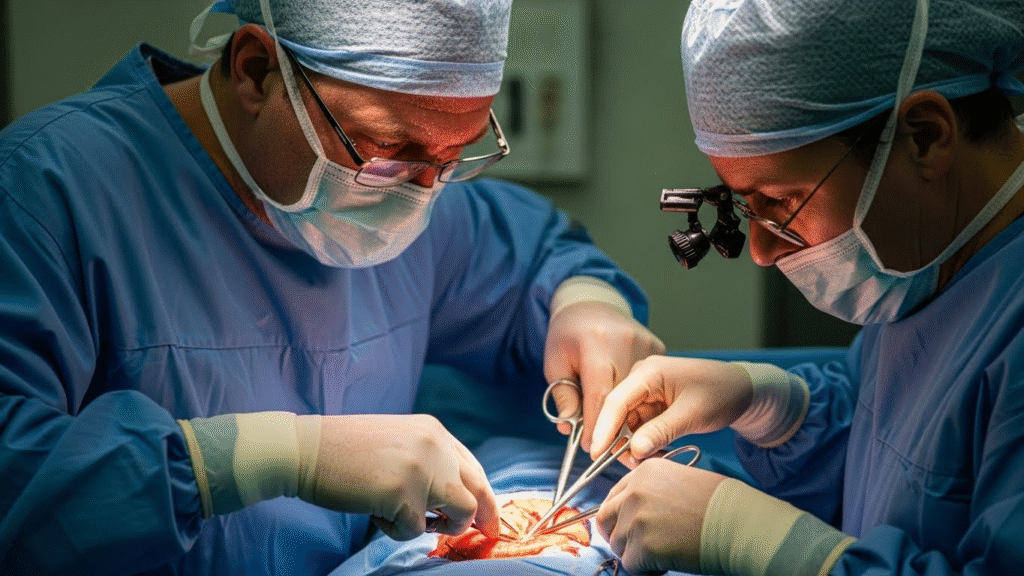

🩺 How Doctors Treat Multi-Cyst Cases Safely

1️⃣ Deep Incision & Drainage

Opening the entire area to reach every sac.

2️⃣ Removal of Each Cyst Lining

If the lining stays, the cyst grows back.

3️⃣ Cleaning the Pocket

Flushing out oil, debris, and infected fluid.

4️⃣ Stitches to Prevent New Pockets

Closing the skin properly reduces future buildup.

5️⃣ Antibiotics for Infection Prevention

Essential because multiple cysts = higher risk.